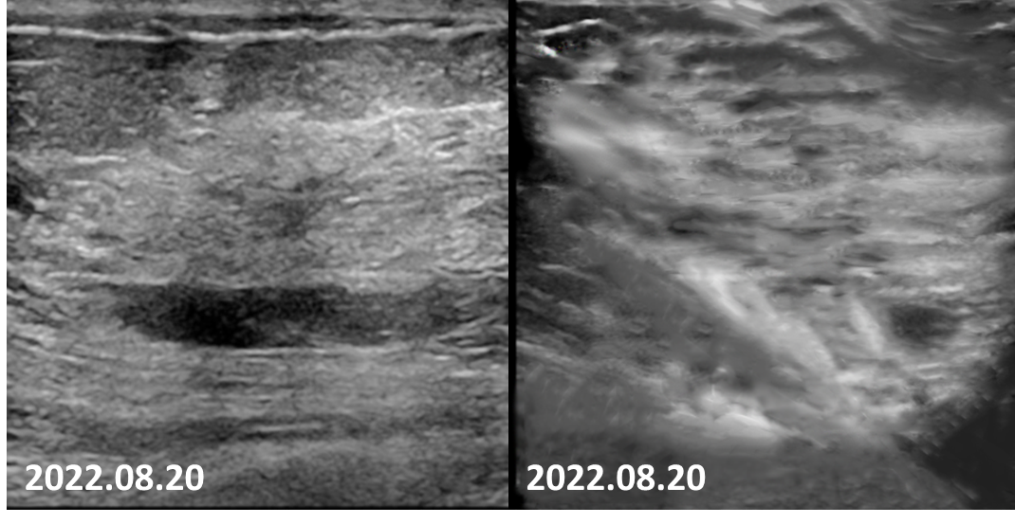

2022-08-20乳腺MRI报告:左乳上方可见点灶状强化,以左乳约3点钟方向稍明显,直径约4mm。大小约24mm×30mm×21mm(上下径×左右径×前后径),病变前缘距乳头约34mm,后缘距离胸壁约11mm。左侧腋窝淋巴结肿大,最大直径约7mm。

图6.4疗程后患者左乳肿物轮廓不明显,左乳肿物及左腋窝淋巴结均无明显增强。

2022-08-20乳腺超声:左乳可见多处低回声结节,较大者位于12点钟,大小约11mm×7mm×11mm,距体表10mm,距乳头35mm,形态不规则,边缘成角,内回声不均匀。CDFI:内可及点状血流信号。左侧腋窝可见数个淋巴结回声,髓质消失,较大者大小约12mm×8mm。CDFI:内可见点状血流信号。右侧腋窝及双侧锁骨上窝未见明显肿大淋巴结。

图8 4疗程后,患者左乳肿物核心基本消失,淋巴结缩小至正常大小。